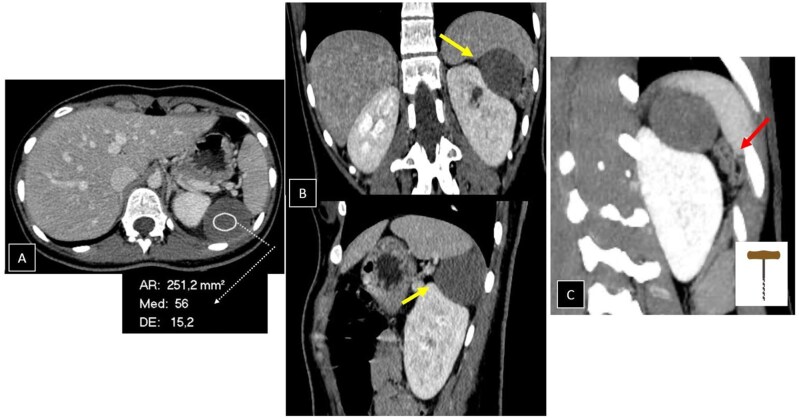

Accessory spleen torsion is a rare but important cause of acute abdominal pain, often presenting with non-specific symptoms that overlap with more common abdominal pathologies. This case report discusses a 19-year-old female who presented with left-sided flank pain and leucocytosis. Imaging with abdominal CT and MRI revealed a well-defined lesion near the spleen and kidney, with mild vascular engorgement and surrounding inflammation. While these findings raised suspicion for accessory spleen torsion, the diagnosis was not immediately clear. The lesion's location, vascular congestion, and absence of typical characteristics for other pathologies, such as haematomas, abscesses, mesothelial cysts, or lymphangiomas pointed towards torsion, but confirmation required surgical intervention. During laparoscopic exploration, a 5 cm accessory spleen with ischaemic changes due to torsion of its pedicle was identified and successfully removed without complications. Accessory spleens, present in 10%-30% of the population, are usually asymptomatic but can become problematic if torsion, rupture, or infarction occurs. Imaging plays a critical role in identifying torsion, with CT and MRI revealing the characteristic "whirlpool sign" and vascular congestion. Early recognition is crucial to prevent complications such as necrosis and rupture, and surgical intervention, typically laparoscopic splenectomy, is the treatment of choice. This case highlights the importance of considering accessory spleen torsion in the differential diagnosis of acute abdominal pain, particularly in young patients with non-specific symptoms. Awareness of this condition can improve early diagnosis and outcomes, preventing severe consequences.

Abstract Image